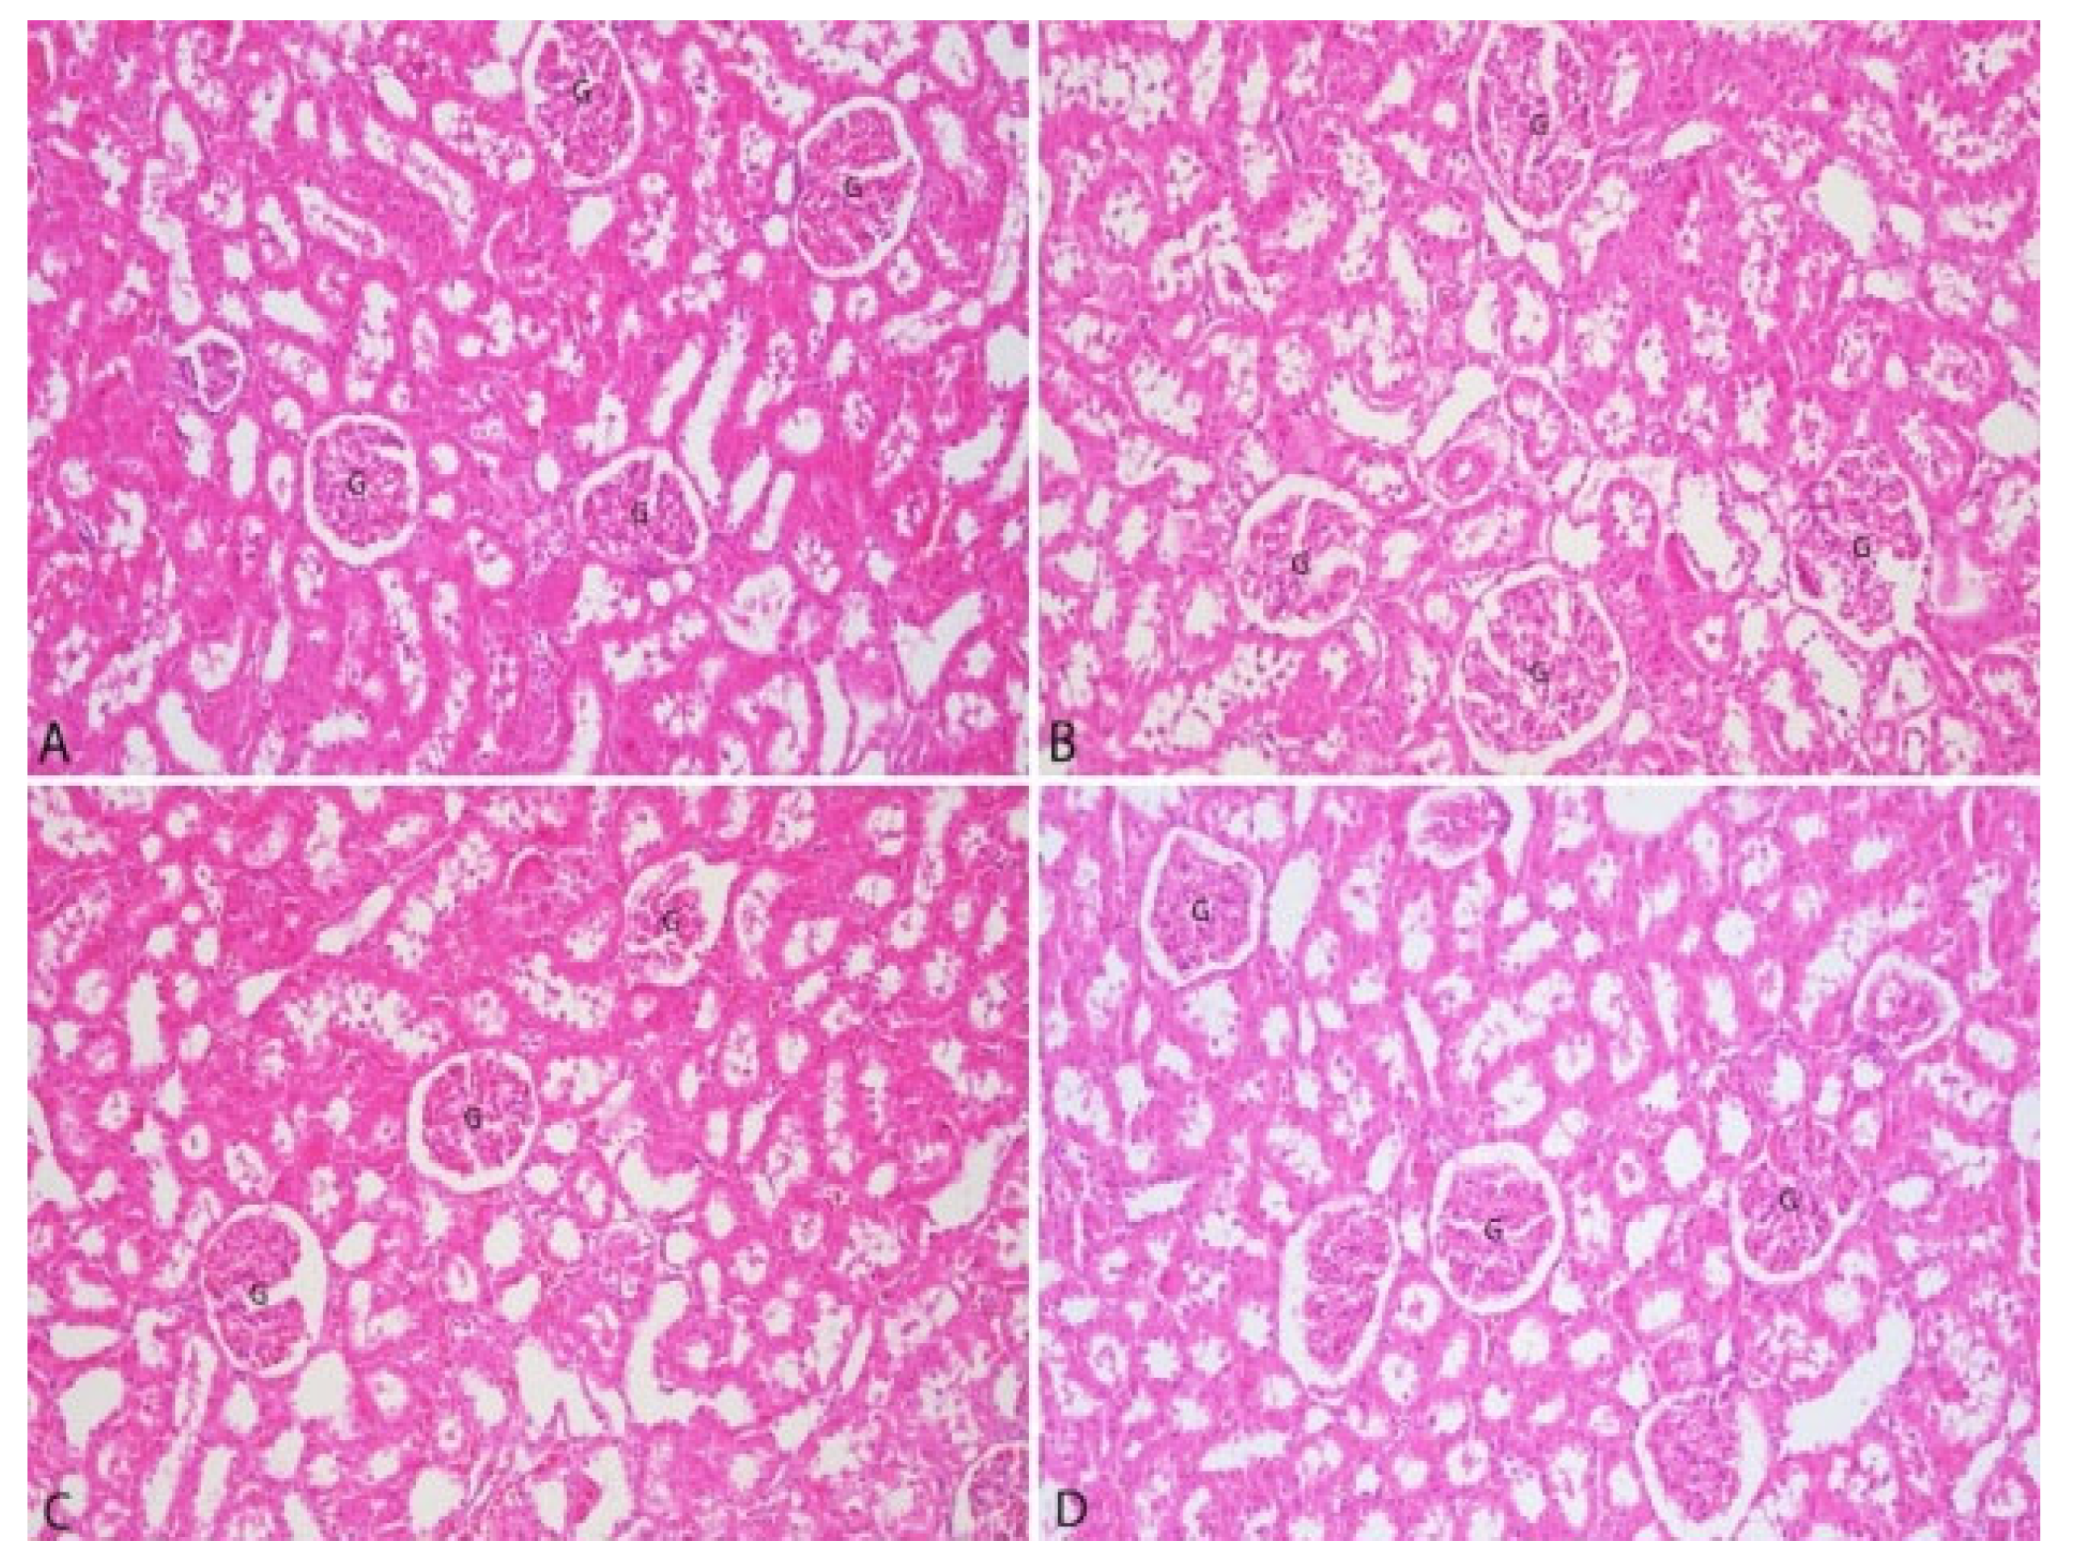

3.3. Pathological Findings